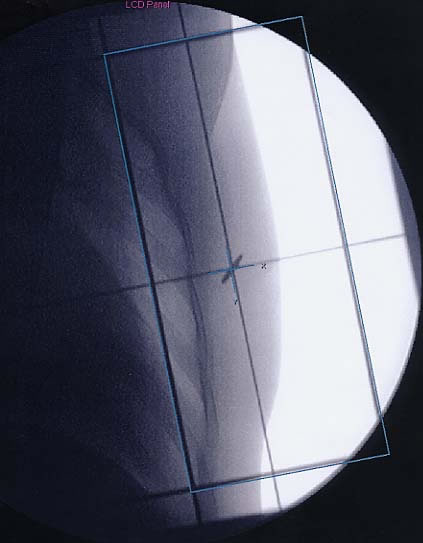

Mammakarzinom: Simulationsbild